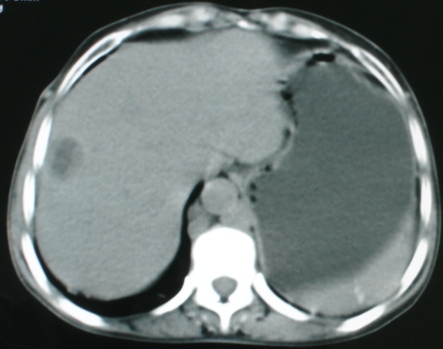

以下是引用zsl6918在2008-11-4 19:14:00的发言:[br]多发转移性改变,子宫改变不除外为原发灶